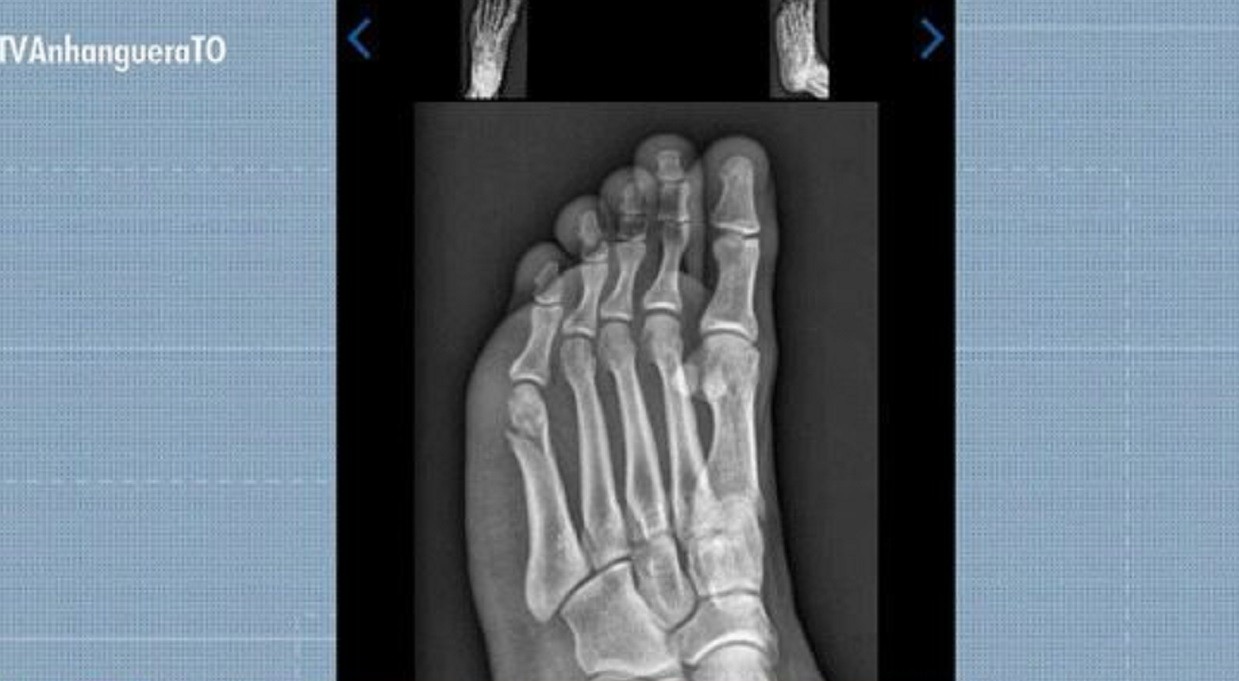

Concurseiro concluiu prova de corrida do TAF com fratura no pé

Reprodução/TV Anhanguera